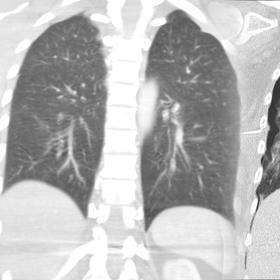

Jak moc koronavirus zasáhne plíce, je patrné na rentgenových snímcích. Když se porovná zdravý orgán se zasaženým, ihned lze vidět výrazný rozdíl. Drobné průdušinky jsou sotva vidět, celkově covidové plíce vypadají na snímcích „zakaleně“, až deformovaně. Proměna, kterou zachycují rentgenové snímky, přitom proběhla přibližně během jednoho týdne.

Podle lékaře, který snímky pro eXtra.cz okomentoval, se plíce nemusí navrátit do normálního stavu, a to ani po úspěšně dokončené léčbě. I to je důvod, proč po prodělání nemoci často přetrvávají následky v podobě respiračních problémů.

„U řady pacientů sledujeme po prodělané infekci změny na plicích. Častěji se jedná o starší lidi, u nichž měla infekce horší průběh. Asi u čtyř procent nemocných, kteří u nás podstoupili podrobné vyšetření kvůli přetrvávajícím postcovidovým problémům, pozorujeme výrazné snížení plicních funkcí,“ vysvětluje primář Kliniky plicních nemocí a tuberkulózy FN Olomouc Milan Sova.